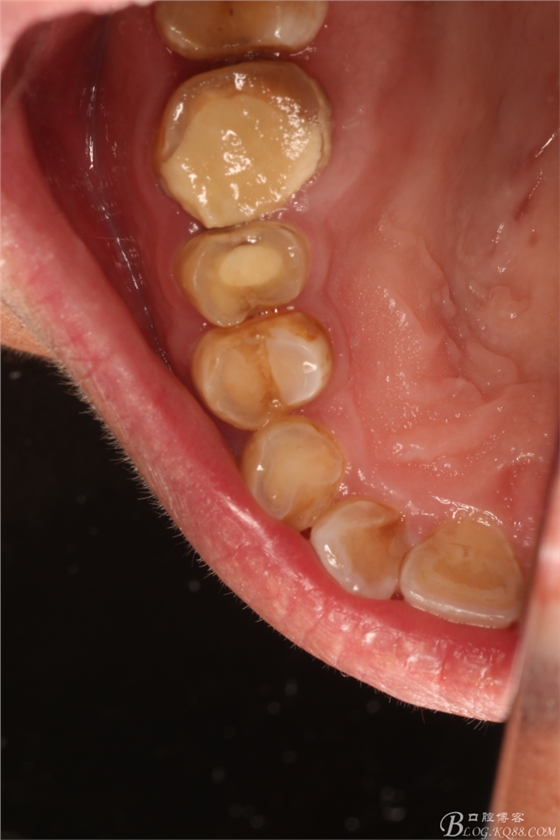

圖2.腭側(cè)未見(jiàn)膨隆,15、16合面均有白色充填物